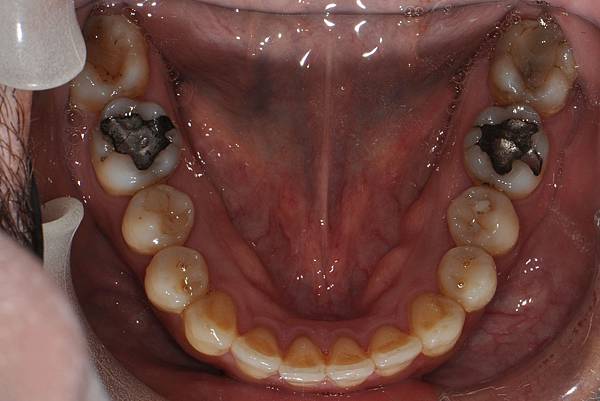

台灣的牙科醫療品質, 連外國人都說讚!此案例為深咬合併二級咬合 林醫師藉由正中上顎骨釘(HPPG technique)做上顎全齒列後移改善暴牙 讓本來五官就相當立體的艾先生,笑起來更燦爛了! 治療前/治療後-以上案例由林昇進醫師提供 分享到